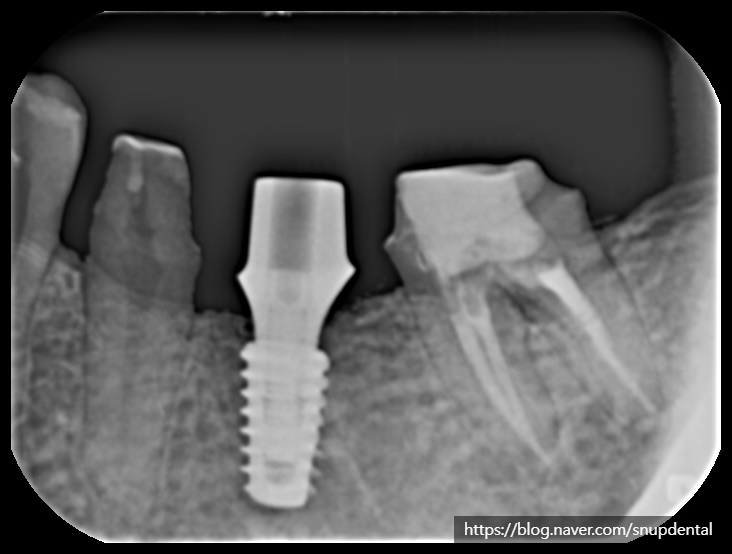

부분 CT 상에서 현재 뼈 상태 및 임플란트 식립 계획을 세워봅니다.

임플란트 수술 후 구강 내 사진 및 부분 CT 캡처 사진입니다